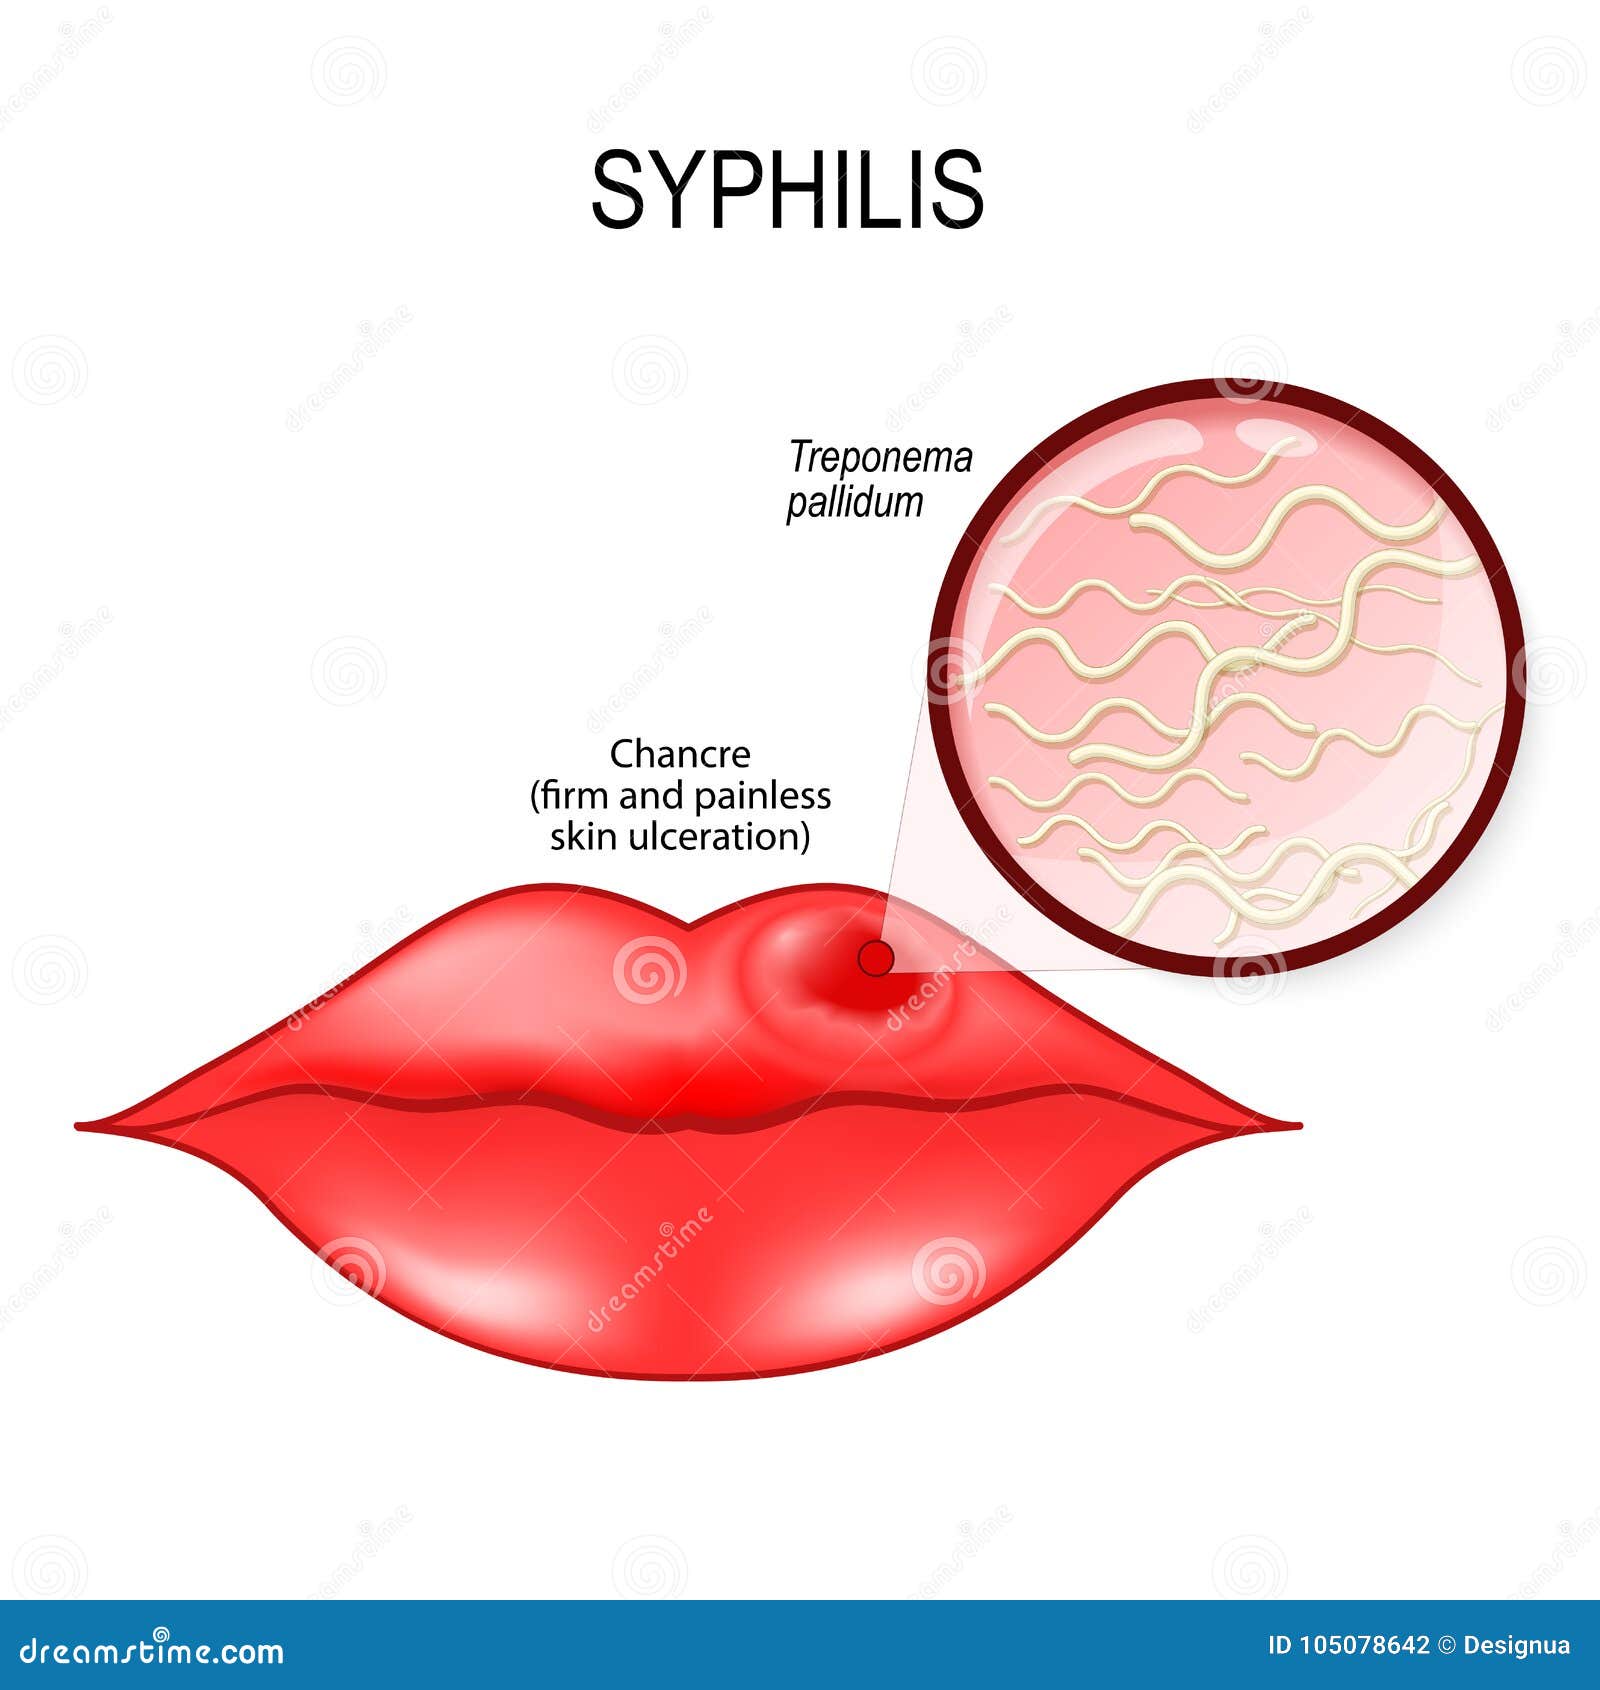

-Syphilitic chancre in oral cavity. | Download Scientific Diagram

Syphilis. Human Lips with Chancre. Treponema Pallidum Stock Vector …

Syphilis Human Lips With Chancre Stock Illustration – Download Image …

The oral manifestations of syphilis. | Download Table